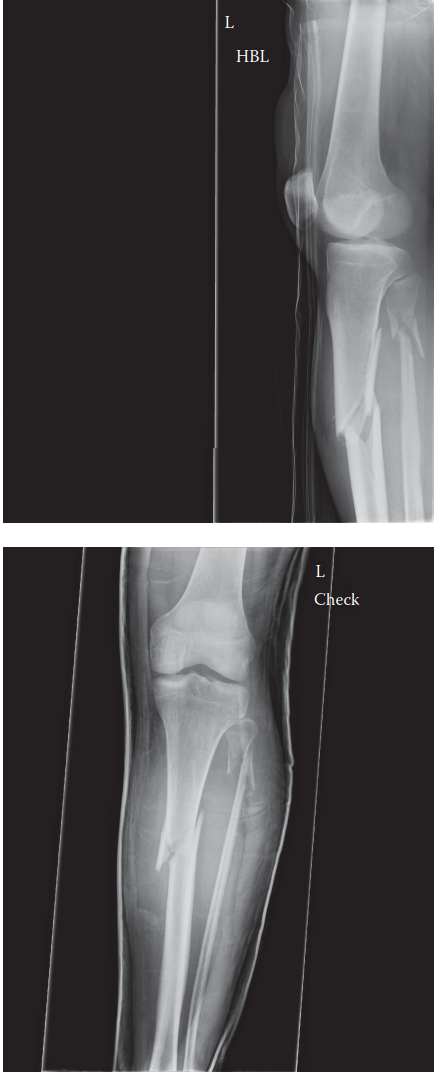

You are the on-call orthopaedic registrar and you are asked to see a young man who has been brought to the em…

Hit the Button to See Answer 1. Can you describe the radiographs? 2. What is responsible for the deformities …

1. Can you describe the radiographs 1. Can you describe the radiographs? ANSWER